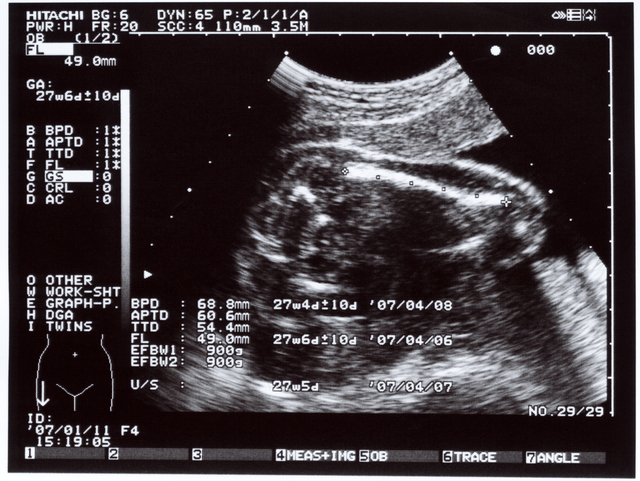

検査写真の中に何回か出てくる「w」や「d」は、妊娠週数(w=week)と日(d=day)をあらわす記号になります。つまり、「32w4d」とあれば、妊娠週数32週4日となります。

後で出てくる様々な記号と値の後に、この数字が出てくる場合はその部位の大きさや長さがその妊娠週数日くらいの大きさ、ということを表しています。

BPDはなに?

BPDは児頭大横径(じとうだいおうけい)、すなわち赤ちゃんの頭の大きさをあらわす数値です。Biparietal(両頭骨頂の) Diameter(直径)の略号となっています。

赤ちゃんの頭を真上から見て、左右の長さと前後の長さを直角に結んだ線の、左右の長さのことです。片方の頭蓋骨の内側からもう片方の頭蓋骨の外側までを結ぶことになっています。

FLは大腿骨長(だいたいこっちょう)をあらわす記号で、Femur(大腿骨) Length(長さ)の略となっています。

大腿骨は太ももの付け根からひざまでの骨のことです。人間の骨の中で一番長い骨と言われ、胎児の発育具合を見る目安とされています。

APTD はなに?

APTDは腹部前後径(ふくぶぜんごけい)をあらわす記号で、Anterior-Posterior(前後) Trunk(胴) Diameter(直径)の略号です。

赤ちゃんの胴体の前後を測った数値になります。

TTD はなに?

TTDは腹部横径(ふくぶおうけい)をあらわす記号で、Transverse(横の) Trunk(胴体) Diameter(直径)の略になります。

赤ちゃんの胴体の左右の長さを測ったものになります。

EFWはなに?

EFWは胎児の推定体重をあらわす記号で、Eestimated(推定) Fetal(胎児の) Weight(重さ)の略となっています。

この値はBPD、AC、FLを使った数式を当てはめて、算出することになっています。